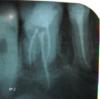

ate Опубликовано 16 сентября, 2009 Поделиться Опубликовано 16 сентября, 2009 (изменено) Здравствуйте!Сегодня хирург поставил перед выбором или удалять зуб (5ка) или резецировать верхушку.Есть ли другие варианты лечения данного случая(консервативно),уж очень не хочется зуб трогать.Зуб беспокоил 3 раза.Первый раз 7 лет назад - был сделан разрез, санация,все стало хорошо.Второй раз беспокоила(болела) 6ка в мае этого года(снимок 1) (разрез,санация - все хорошо), третий раз тоже 6ка резать не стали ибо был инфильтрат,вылечила консервативно(аб,полоскание итп).Снимок № 2 - настоящий момент. Врач говорит,что виновата во всех трех случаях 5ка (в последних двух была иррадиация боли на 6ку)..Врачи говорят каналы хорошо запломбированы, причину воспаления назвать не могут.Делать не делать резекцию??А где гарантия что 6ка не даст воспаление?Помогите пожалуйста ибо зуб болит невыносимо (кетанова в инъекциях хватает на 4 часа)Спасибо за внимание! Изменено 16 сентября, 2009 пользователем ate Ссылка на комментарий

Scrabble Опубликовано 16 сентября, 2009 Поделиться Опубликовано 16 сентября, 2009 На снимке в косой проекции 4-ый канал в 6 видно. Остальное см. Annda и dr. Stom Ссылка на комментарий